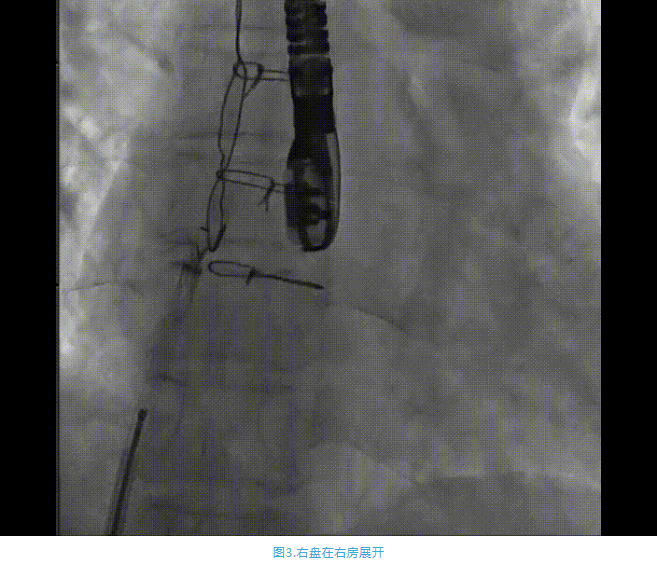

術(shù)中首先在局麻下穿刺股動(dòng)脈、股靜脈,完成心導(dǎo)管檢查評(píng)估后轉(zhuǎn)為全麻,在食道超聲引導(dǎo)下穿刺房間隔,穿刺成功后將加硬導(dǎo)絲送入左上肺靜脈建立軌道,根據(jù)患者病情行球囊預(yù)擴(kuò)張后植入6mm孔徑房間隔造孔支架,經(jīng)透視及食道超聲評(píng)估支架左右盤展開良好,夾持于房間隔兩側(cè),固定穩(wěn)定、位置良好,食道彩超顯示房水平右向左為主分流,分流孔直徑符合預(yù)期大小,心導(dǎo)管檢查評(píng)估達(dá)到預(yù)期效果,釋放造孔支架。術(shù)后12h患者下床活動(dòng),恢復(fù)順利,擬于近日完善術(shù)后評(píng)估后出院。